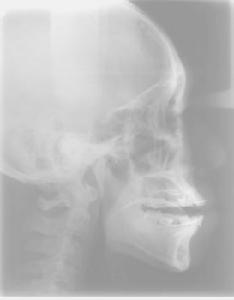

X線頭影測量

為了間接了解氣道,以及檢查氣道阻塞部位,並且對OSAHS作出初步診斷,X線頭影測量很重要。用於測量氣道和相關的數值包括:

①∠SNA,表示上頜骨對顱底的相對位置。

②∠SNB,表示下頜骨對顱底的相對位置。

③∠ANB,代表上下頜骨相對位置關係。

④PNS-P,後鼻嵴點(PNS)到軟齶末端齶垂(P)的長度,代表軟齶長度。

⑤PAS,為舌根至咽後壁間的距離,代表後氣道間隙,又稱生命間隙。

⑥MP-H,下頜平面至舌骨最前最上點(H)的距離,代表舌骨的位置。

⑦SPD,代表軟齶外形最寬距離,表示軟齶的厚度。

根據盧曉峰和邱蔚六等的研究報導,RDI與PAS成顯著負相關關係。當PAS≥9.12mm時,RDI的值95%可能小於5;而PAS≤4.61mm時,則相反,RDI的值95%可能大於5。伊彪和張震康等的研究報導,OSAHS患者的SNA角基本正常,表明上頜位置正常;SNB角明顯減小,表示下頜明顯後縮;ANB角明顯增大,表明下頜骨相對上頜骨明顯處在後縮位置;PAS明顯減小,下咽部氣道狹窄;MP-H增大,表明舌骨低於低位;PNS-P大部分正常。